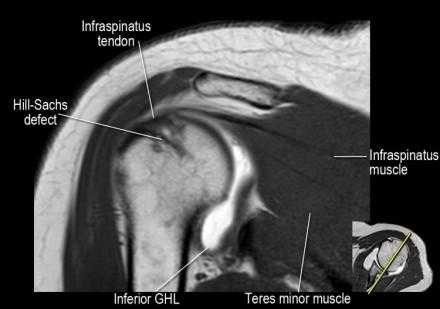

- обратите внимание на верхние отделы суставной губы и прикрепление верхней плече-лопаточной связки. На данном уровне ищется SLAP-повреждение (Superior Labrum Anterior to Posterior) и варианты строения в виде отверстия под сутавной губой (sublabral foramen - подгубное отверстие). На этом же уровне по задне-боковой поверхности головки плечевой кости визуализируются повреждение Хилл-Сакса.

- вогнутость заднебокового края головки плечевой кости не следует путать с повреждением Хилл-Сакса, поскольку это нормальная форма для данного уровня. Повреждение Хилл-Сакса визуализируется только на уровне клювовидного отростка. В предних отделах мы сейчас на урвоне 3-6 часов. Здесь визуализируются повреждение Банкарта и его варианты.

- обратите внимание на небольшое повреждение Хилл-Сакса